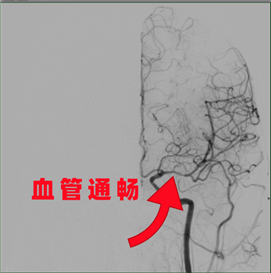

手术室中,一场无声的“生命抢夺战”打响。神经内科介入手术组组长缪桂华副主任医师团队通过微创介入技术,将一根细小的导管从股动脉送入,精准地抵达大脑中动脉堵塞处。小心翼翼地,开通了闭塞的大脑中动脉。瞬间,被阻断的血管再次恢复了奔流,缺血已久的脑组织重新获得了滋养。手术顺利成功!